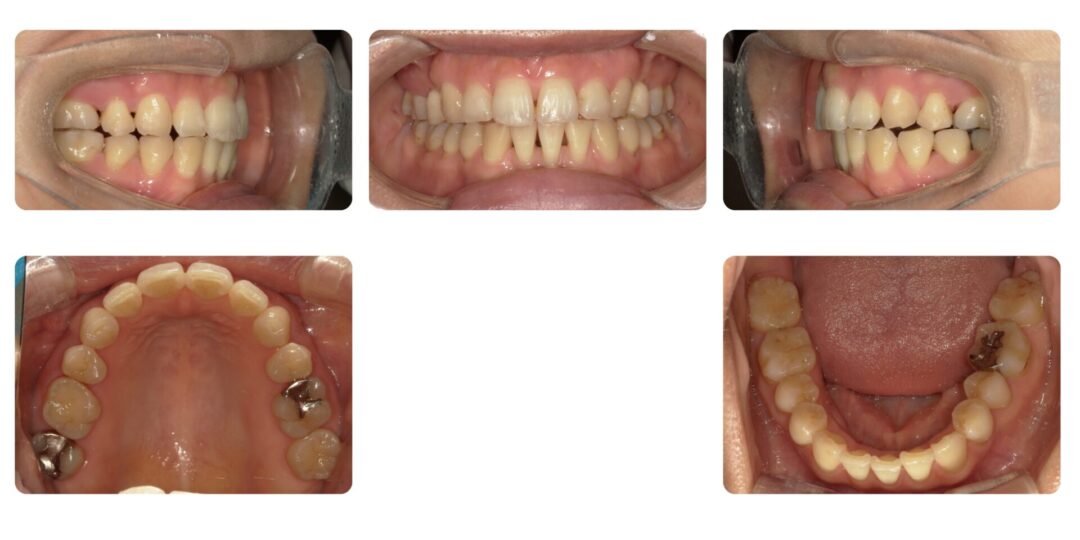

矯正治療前

初診時34歳

治療内容

成人矯正 左右第一小臼歯、右下側切歯抜歯 マルチブラケット矯正

治療期間

3年7ヶ月

治療費用

自由診療 基本料金 審美ブラケット¥770,000(初診時)、処置料¥5,500

アンカースクリュー埋入(2本)¥22,000